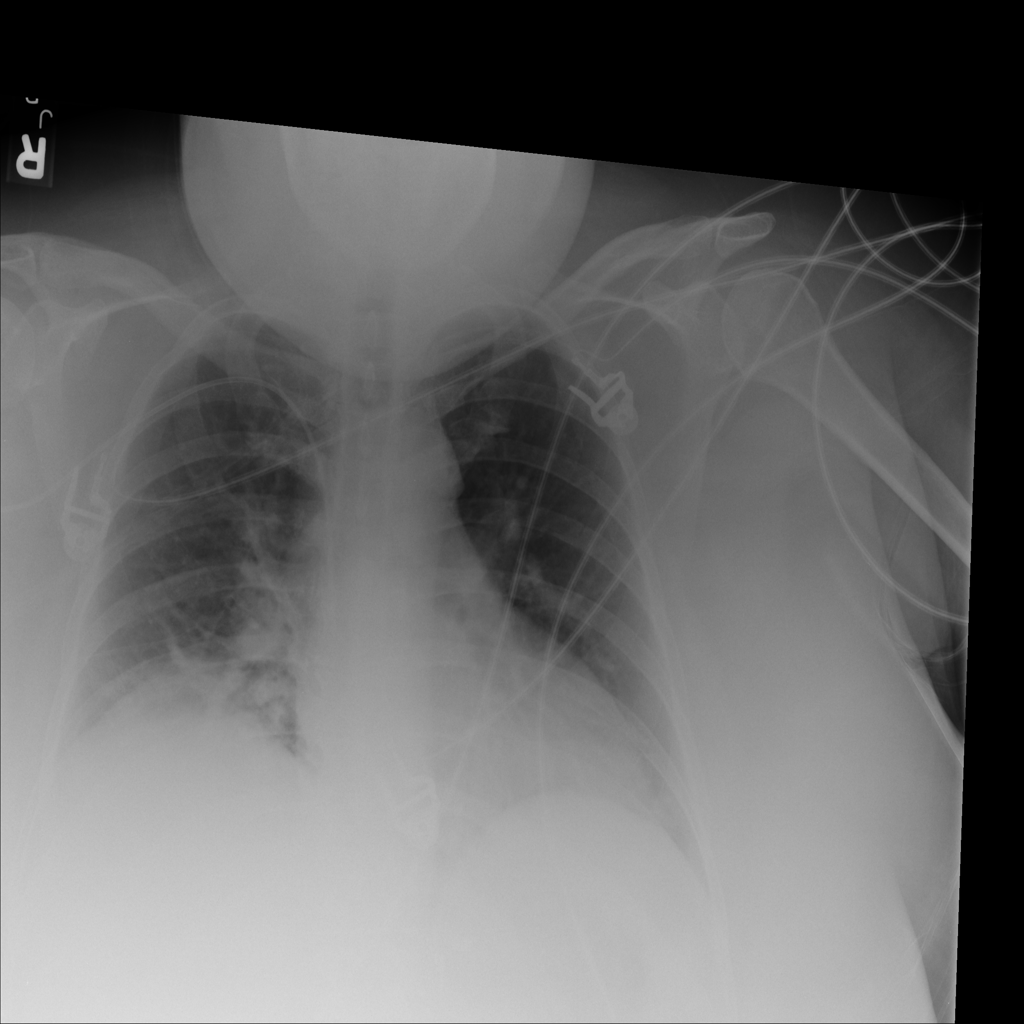

PAT-BA30 · IMG-001Atelectasis

PAT-BA30 · IMG-001

PA